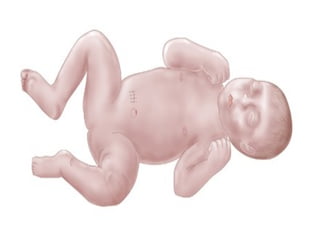

• Lump in the abdomen

• Intestine sticks through the abdominal wall

near the umbilical cord

• Problems with movement and absorption in

the gut due to the unprotected intestine

being exposed to irritating amniotic fluid

Symptoms • Lump inthe abdomen • Intestine sticks through the abdominal wall near the umbilical cord • Problems with movement and absorption in the gut due to the unprotected intestine being exposed to irritating amniotic fluid